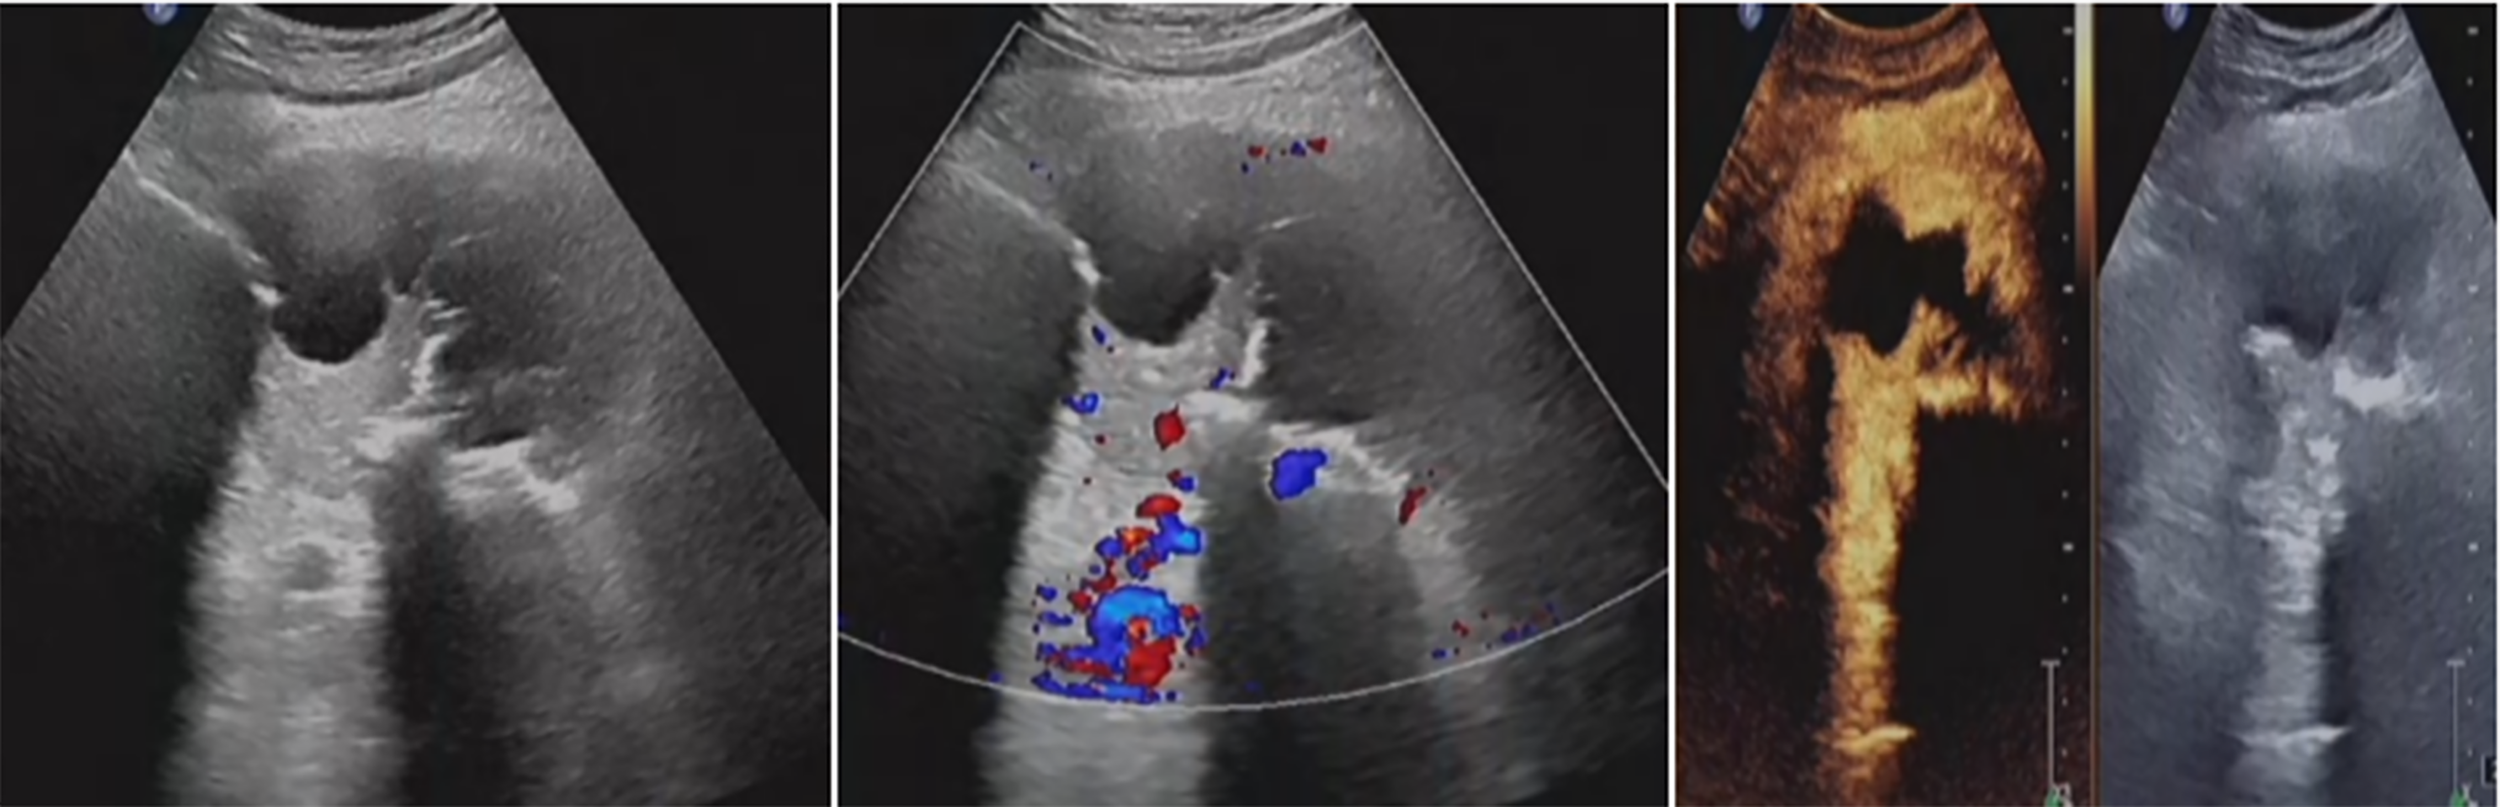

Figure 6

Residual tumor was inactivated by ultrasound-guided fractionated radiofrequency ablation. The ablation range was preliminarily estimated to reach 90%, achieving the expected therapeutic goal.